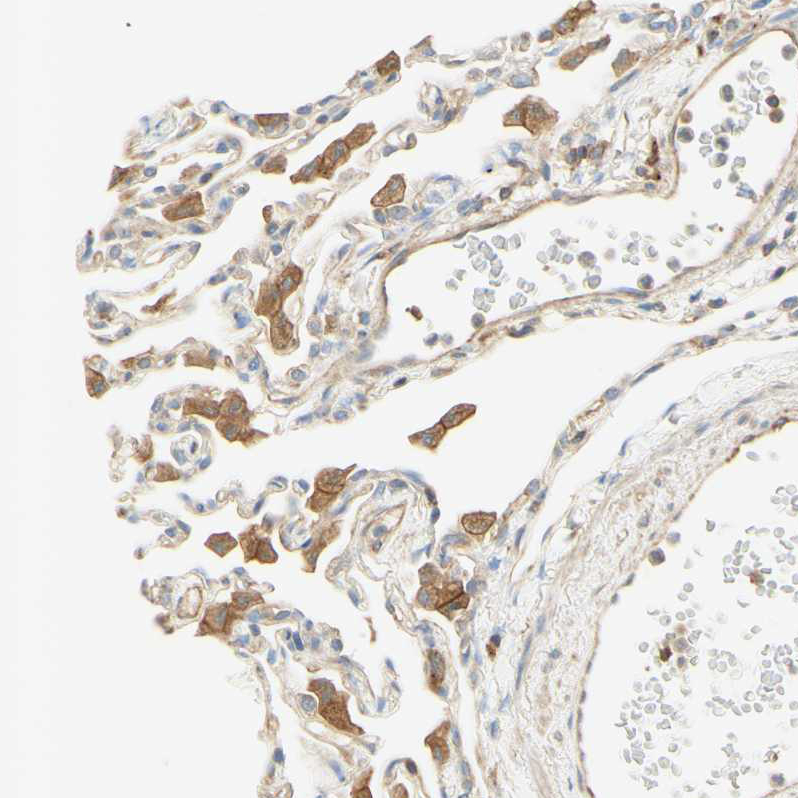

Immunohistochemical staining of human lung shows moderate cytoplasmic positivity in macrophages.